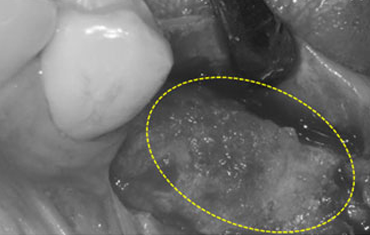

램브란트치과 상인점 뼈이식 후 골조직